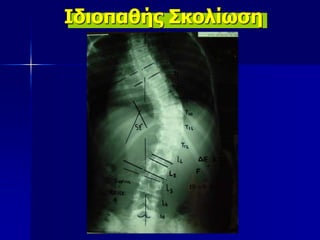

6.

Ιδιοπαθής Σκολίωση